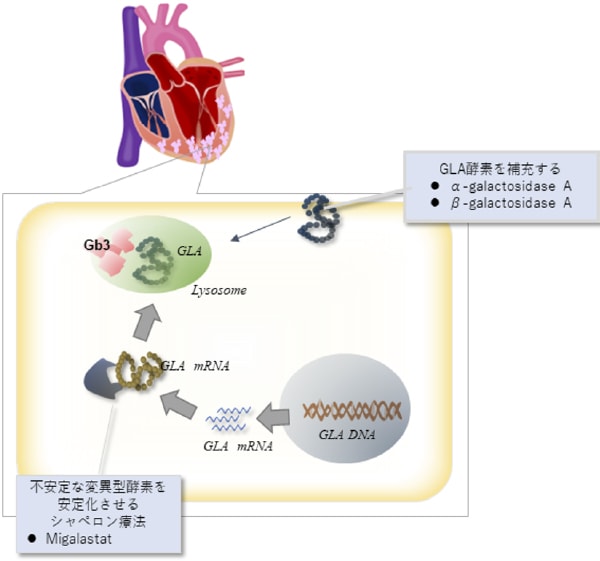

ファブリー病は遺伝性疾患です。Alpha-galactosidase A (GLA)という酵素の働きが悪く、心臓以外に、腎臓や末梢神経にglobotriaosylceramide (Gb3)という糖脂質が蓄積します。心臓に関しては初期は心肥大、進行すれば線維化が起こります。診断はalpha-galactosidase活性以外に、心臓MRIなどの画像検査、心筋生検や遺伝子検査が有用です。

ファブリー病に対して、酵素補充療法は以前から行われている有効な治療です。一部の変異型にはシャペロン療法という酵素の安定化をたすける治療が可能です。